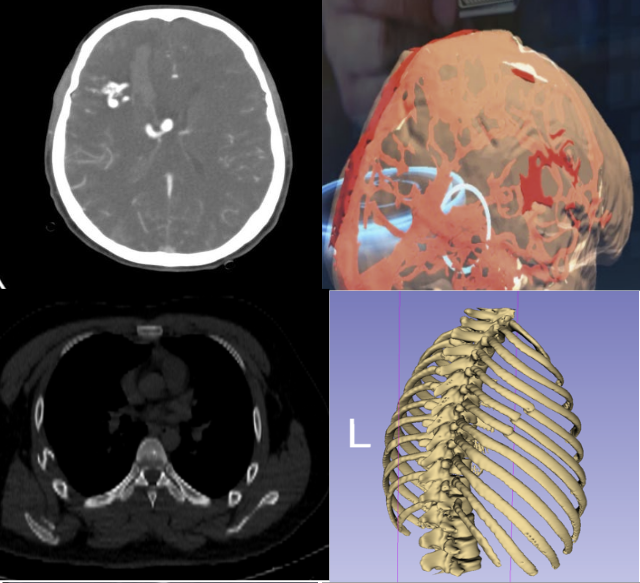

Deep learning, a subset of machine learning, is particularly useful in image recognition and analysis, which can be critical in diagnostics. For example, deep learning models can analyze X-rays, CT scans, and other imaging modalities to assist in diagnosing conditions quickly and accurately.